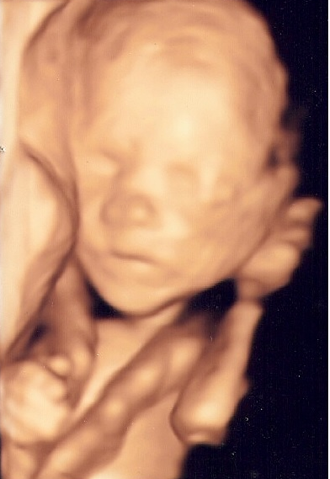

Alles bleibt anders - Tagebücher aus der Schwangerschaft von Jana aus Südthüringen